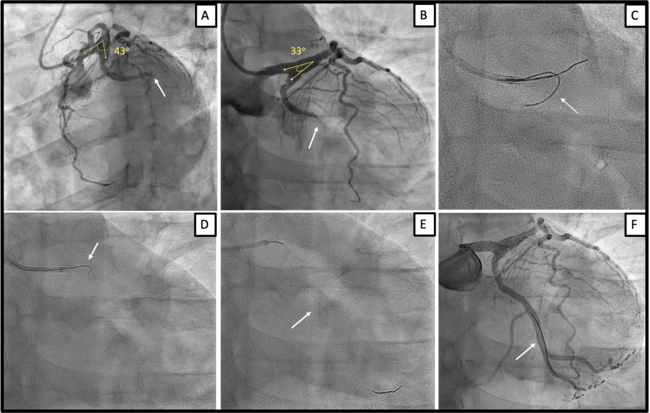

A 50-year-old man with a family history of coronary artery disease underwent primary percutaneous coronary intervention (PPCI) due to an inferior ST-elevation myocardial infarction (STEMI). Coronary angiography revealed an occluded left circumflex artery (LCx) (Figure A, arrow).

Wiring of the LCx proved impossible due to an extremely acute bifurcation angle between the left main artery (LM) and the LCx, measuring 43° in left anterior oblique and 33° in anteroposterior caudal projections (Figure A and B, Video 1). The hairpin bifurcation of the LM/LCx and the presence of proximal ectasia caused guidewire prolapse to the LAD. Despite the use of a dual lumen microcatheter, the guidewire could not be advanced into the LCx and prolapsed to adjacent branches (Figure C, arrow).

We aimed to utilize a Venture steerable microcatheter (SM) (Teleflex) to steer its tip to the LCx ostium. The SM was advanced up to the ostial LAD over a guidewire. Subsequently, the guidewire was retracted, and the tip of the SM was carefully deflected at an angle of 90° while the shaft was torqued to the LCx ostium (Figure D, arrow; Video 2). This maneuver requires caution to avoid microcatheter-induced coronary dissection. With the SM in place, adequate support was provided to navigate the guidewire to the LCx (Figure E, arrow; Videos 3 and 4). PPCI with stent implantation was performed (Figure F, arrow). The clinical course was uneventful, and the patient was scheduled for staged PCI of the LAD and right coronary artery.